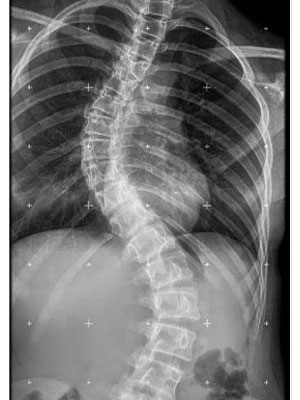

¿Cómo se ve la escoliosis en la radiografía?

• La escoliosis viene definida por la región de la columna vertebral donde surge la curva (columna torácica alta, columna torácica o columna lumbar).

• La escoliosis puede localizarse en uno o más segmentos: curva simple, curvas dobles o triples.

• La dirección de la curva puede ser derecha o izquierda.

La escoliosis puede localizarse en uno o más segmentos: curva simple, curvas dobles o triples. La dirección de la curva puede ser derecha o izquierda.

Ejemplos de diferentes curvas y diversas localizaciones.